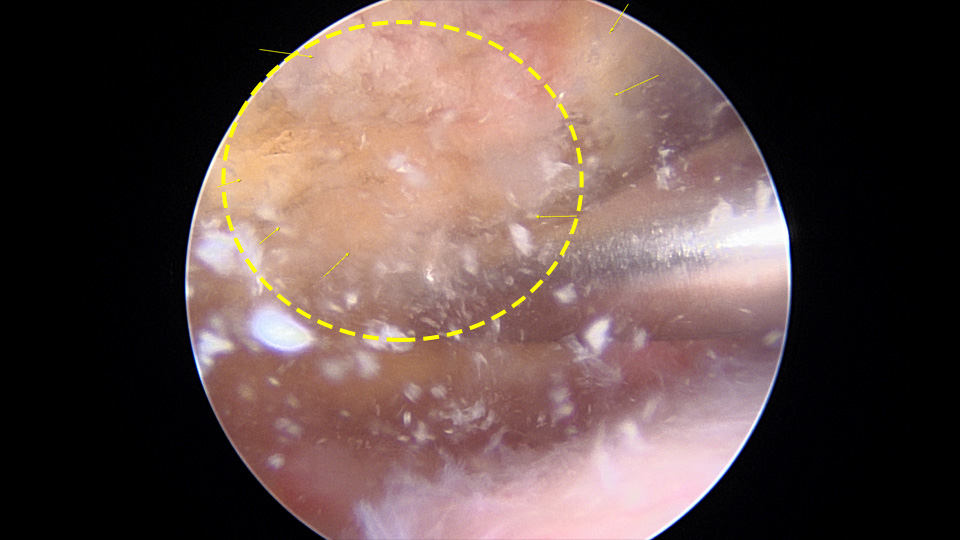

3. 수술치료

심한 경우, 또는 회전근개 손상이 동반된 경우, 또는 위와 같은 치료에 반응하지 않을 때는 관절경을 이용해서 수술적으로 제거하기도 합니다.

• 관절경 수술

주위 조직 즉, 회전근개의 손상없이 석회만 제거하는 것이 수술의 주요 관점입니다.

어깨 관절경을 이용해서 석회질을 제거할 수 있다.

- 환자 동의하에 게시된 이미지입니다.